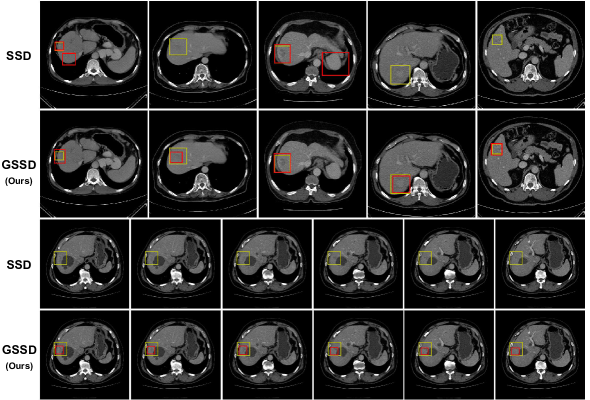

By significantly suppressing overfitting of the class confidence layers (Figure 3), our grouped SSD (GSSD) outperformed the original model as well as recently proposed state-of-the-art variants (Table 1) [18, 19]. Figure 4 demonstrates qualitative detection results. The best configuration achieved a 53.3% average precision (AP) score (Table 1). The model runs approximately 40 slices per second and can go through an entire volume of 100 slices in under three seconds on an NVIDIA Tesla P100 GPU. Note that the 1x1 convolutions play a key role as channel selectors. GSSD failed to perform well without the module. Stacking the 1x1 convolutions on top of the original model did not improve its performance, which proved that the combination of grouped convolutions and the channel selector module best harnesses the multi-phase data distribution.